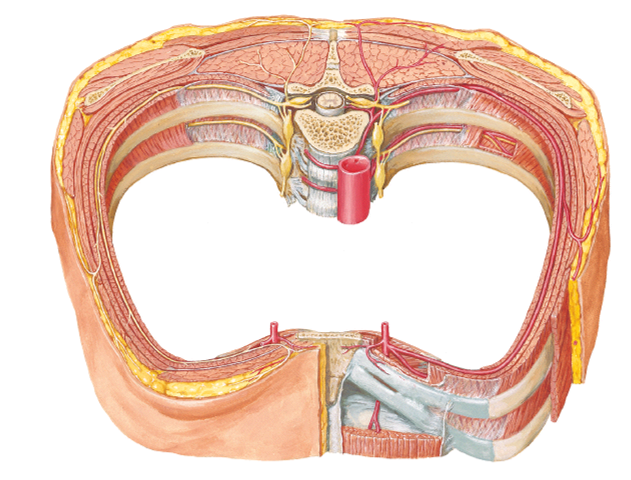

Identify/describe the intercostal artery pathway?

- Intercostal arteries/veins run in the ___________ aspect of

the intercostal space?

- They are ________ to the “superior rib” of the intercostal space?

- Collateral branches of intercostal arteries/veins run in the _________ aspect of the intercostal space

superior aspect

inferior

inferior

describe whats in the intercostal spaces from superior to inferior?

These travel in intercostal space together just ________ to rib

- There is a second set of smaller collaterals located ________ to each rib

- Vein

- Artery

- Nerve

inferior

superior

notice in picture how the vein artery and nerve (VAN) is just below the rib and then more down in the intercostal space just above the rib are the collateral vessels

vein, artery and nerves are located just ______ each rib?

what is a thoracentesis? what do you want to avoid when you insert the needle? overall, where do you wanna put the needle?

below

- Procedure to remove fluid from pleural cavity

- Avoid damage to intercostal structures (and lung) when inserting needle

put the needle on the superior margin of the rib...avoids hitting the VAN's